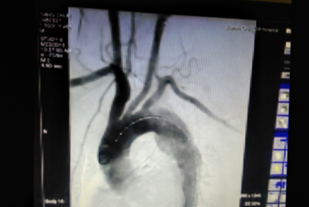

術(shù)后(見主動脈血流規(guī)則,治療效果良好)

“微創(chuàng)腔內(nèi)治療技術(shù)給患者帶來了福音?!蔽河钫f。手術(shù)僅需行腹股溝部的小切口,在X線監(jiān)視屏監(jiān)測下通過微創(chuàng)介入的方法將覆蓋人工血管的金屬支架精確植入到有問題的血管,從而將血流與問題管壁隔絕。手術(shù)難度很大,風(fēng)險極高,醫(yī)生操作需要非常謹慎,支架需精確植入到病變位置。手術(shù)能實現(xiàn)與開腹手術(shù)相同的治療效果,但避免了開腹手術(shù)引起的創(chuàng)傷及相關(guān)并發(fā)癥,術(shù)后恢復(fù)時間也遠遠短于外科手術(shù),一般2-3天即可。